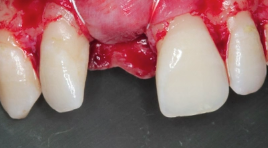

CLINICAL VIDEO Esthetic Implant Placement with Simultaneous GBR and Soft Tissue

CAT# CV-090

Esthetic Implant Placement with Simultaneous GBR and Soft Tissue Graft to Treat a Partially Failed Previous Bone Graft

Dr. Sascha A. Jovanovic

CLINICAL VIDEO Anterior Implant Placement with Simultaneous GBR using Autogenous

CAT# CV-085

Anterior Implant Placement with Simultaneous GBR using Autogenous/Xenograft and Native Collagen Membrane